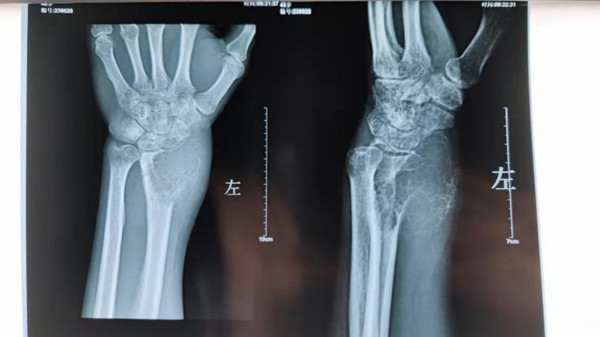

术前X线片

患者刘某三个月前发现左腕部长出一个硬硬的包块,外院诊断为恶性肿瘤,已决定截肢。随后到我院门诊挂号就诊,接诊的宋金辉教授初步诊断为骨巨细胞瘤。

骨巨细胞瘤(Giant Cell Tumor of Bone,GCTB)是一种交界性的原发骨肿瘤,疾病具有侵袭性,可局部复发和远处转移,好发生于青壮年,20~40岁为发病高峰,在四肢长骨中,股骨远端、胫骨近端、桡骨远端和肱骨近端最为多见,骨盆和脊柱等中轴骨也常受累。常规刮除术后有较高的局部复发率,肺转移率1%~9%。极少数病例可转化为高度恶性骨肉瘤,预后差。